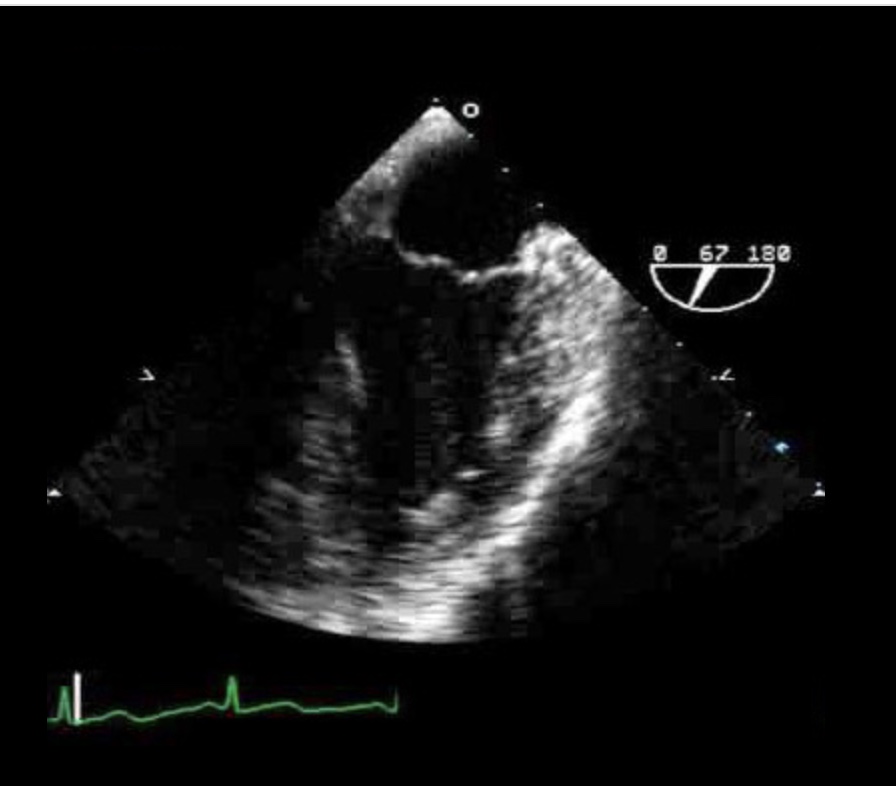

What TEE view is this? ID the structures

ME MV commissural view

LA & LV

Coronary sinus

Anterior and posterior leaflets of MV

Papillary muscles

Chordae tendinae